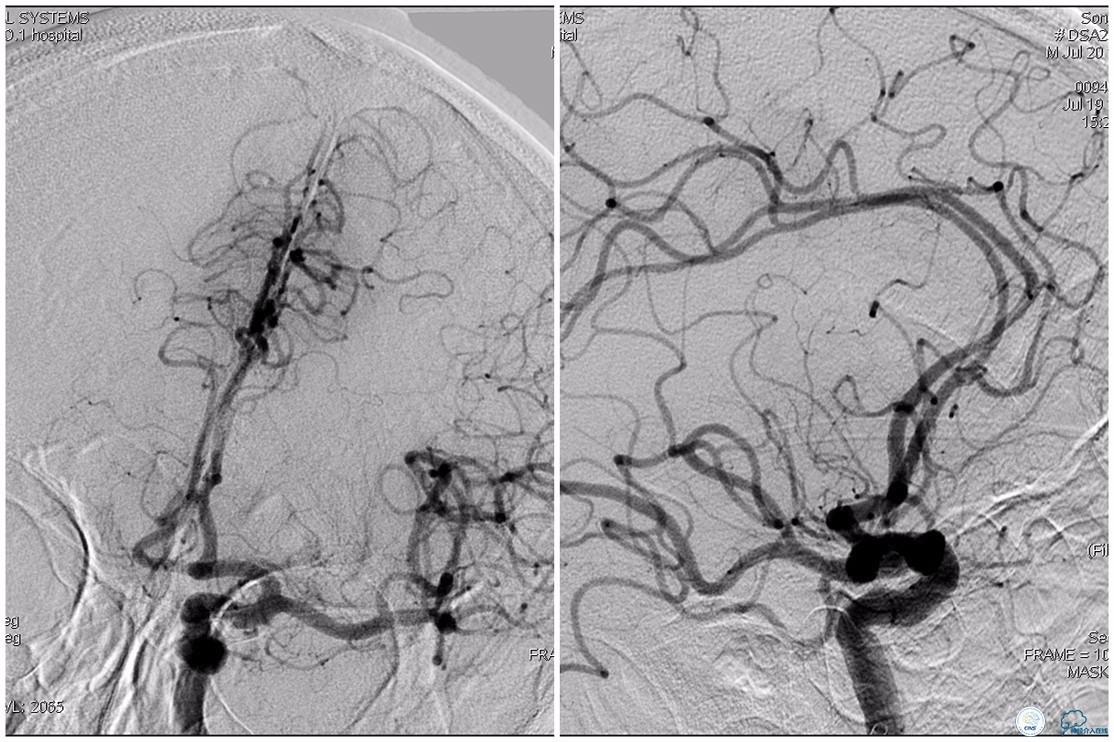

12:35穿刺成功,TOT 185min。3型主动脉弓,右侧颈内动脉起始部狭窄70%,右侧大脑前动脉A1段未显影。

双侧大脑前动脉A4段闭塞,右侧大脑前动脉由左侧大脑前动脉经前交通动脉代偿供血。

6F Envoy置于颈内动脉C3段,选用Solitaire-FR 4*20mm支架释放于右侧大脑前动脉,完全覆盖血栓。

6F Envoy置于左侧颈内动脉C3段,选用Solitaire-FR 4*20mm支架释放于右侧大脑前动脉取栓1次,血流达TICI 2b。

Solitaire-FR 4*20mm支架释放于左侧大脑前动脉取栓1次,取出少许血栓重复造影左侧大脑前动脉胼周动脉开口后,右侧大脑前动脉A2段以远未显影,考虑栓子逃逸。

选用Solitaire-FR 4*20mm支架分别于右侧大脑前动脉A2-A3段,左侧胼周动脉,右侧胼周动脉取栓3次。

双侧大脑前动脉完全显影,TICI 3级,TOR 261min。